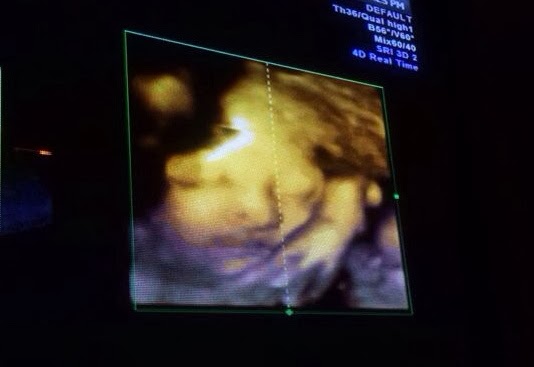

昨天再去覆診,BB十分健康。而且今次終於可以看到他的整張臉了!每次照4D,他都會用手遮著臉,真是十分神秘。今次開始時也是這樣,到過了一會,看見他打呵欠,才見到他的真面目... BB有個很高很大的鼻子,哈哈大鼻像我高鼻像老外榮。輪廓很分明,應該也是"靚仔"一名啦。其實之前幫KEON擇日時,已經大約知道他是一個怎樣的人。知他應該桃花很重,有點脾氣及反叛受軟不受硬,要講道理<---這個似媽咪。其實最重要是他可以身體健康,亦要做一個好人便夠了。... 看全文 -